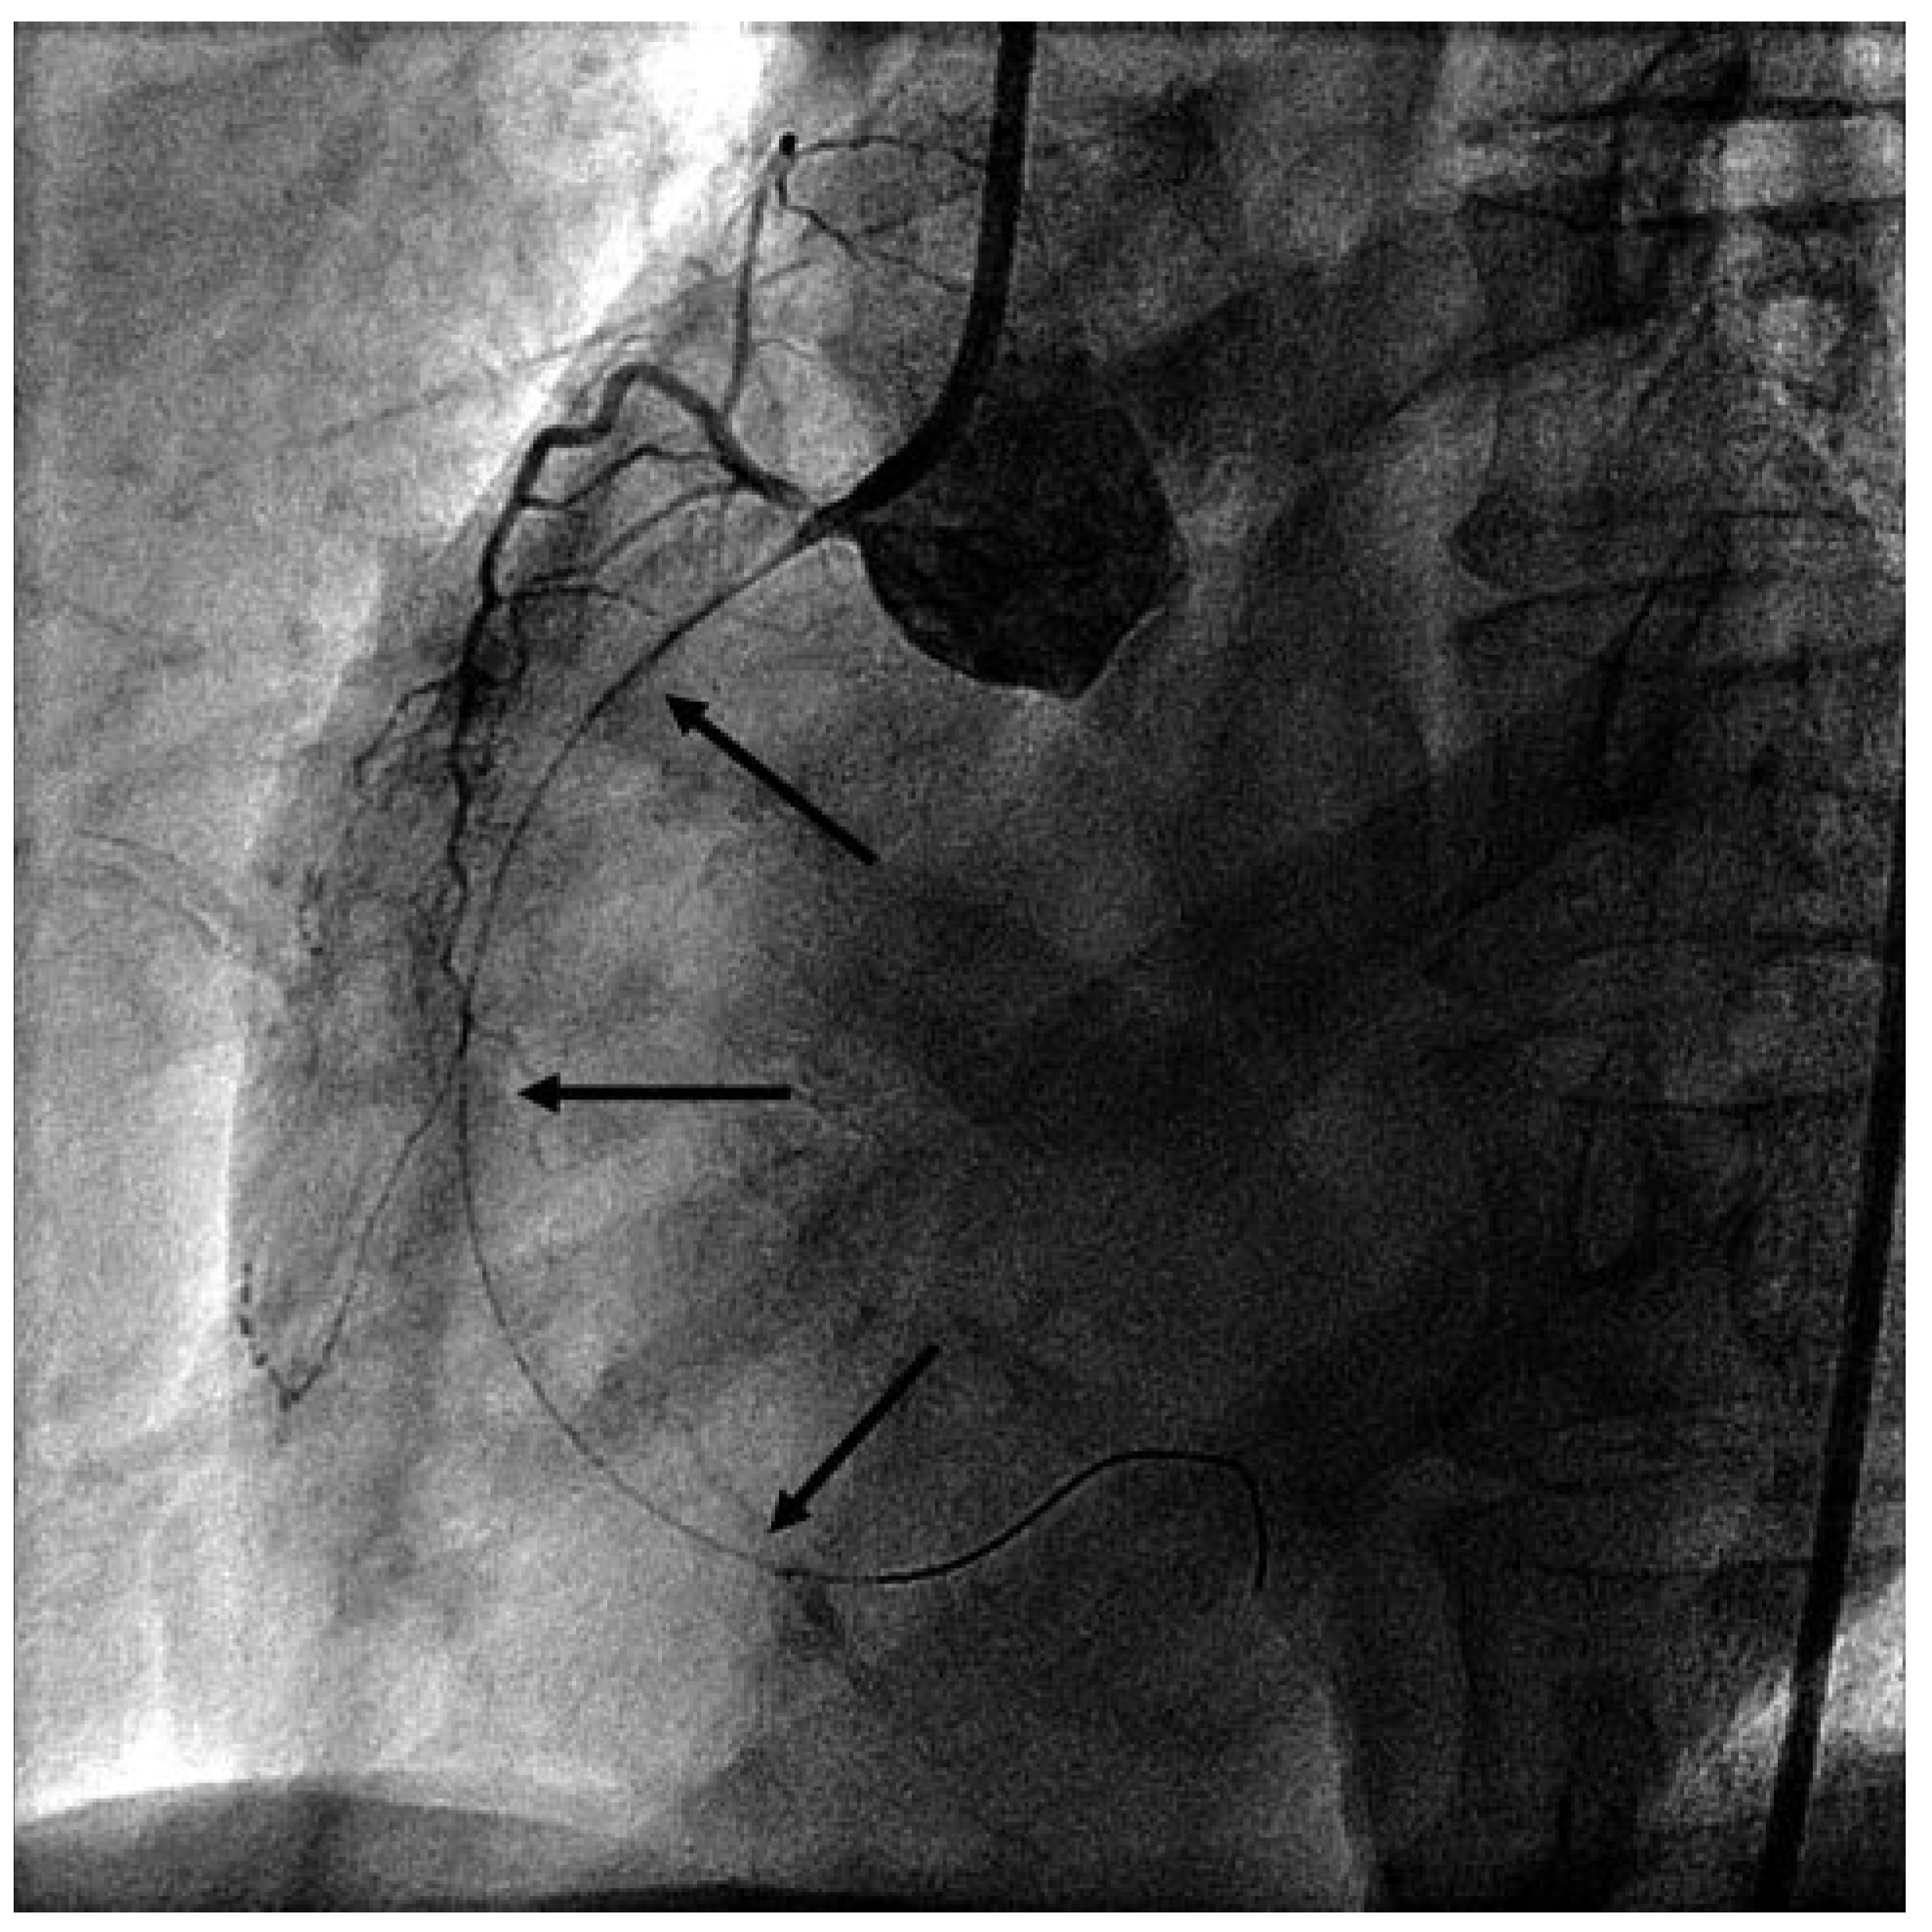

Due to further haemodynamic deterioration an intraaortic balloon pump was placed. At this point review of the angiogram led us to suspect spasmodic occlusion of the RCA due to guide catheter and wire irritation. Intracoronary nitroglycerin (NTG), adenosin and verapamil were administered. The wire was pulled as far as the mid-RCA, after which measures flow was restored in the RCA (Figure 3) and the patient’s haemodynamic status stabilised. Reangiography of the left coronary artery showed resolution of the previously observed spasmodic lesions, and finally variant angina (prinzmetal angina) was diagnosed.

Figure 3. LAO view of the RCA: patent artery after injection of intracoronary nitroglycerin and verapamil and after pulling back of the coronary guidewire as well as the guide catheter.